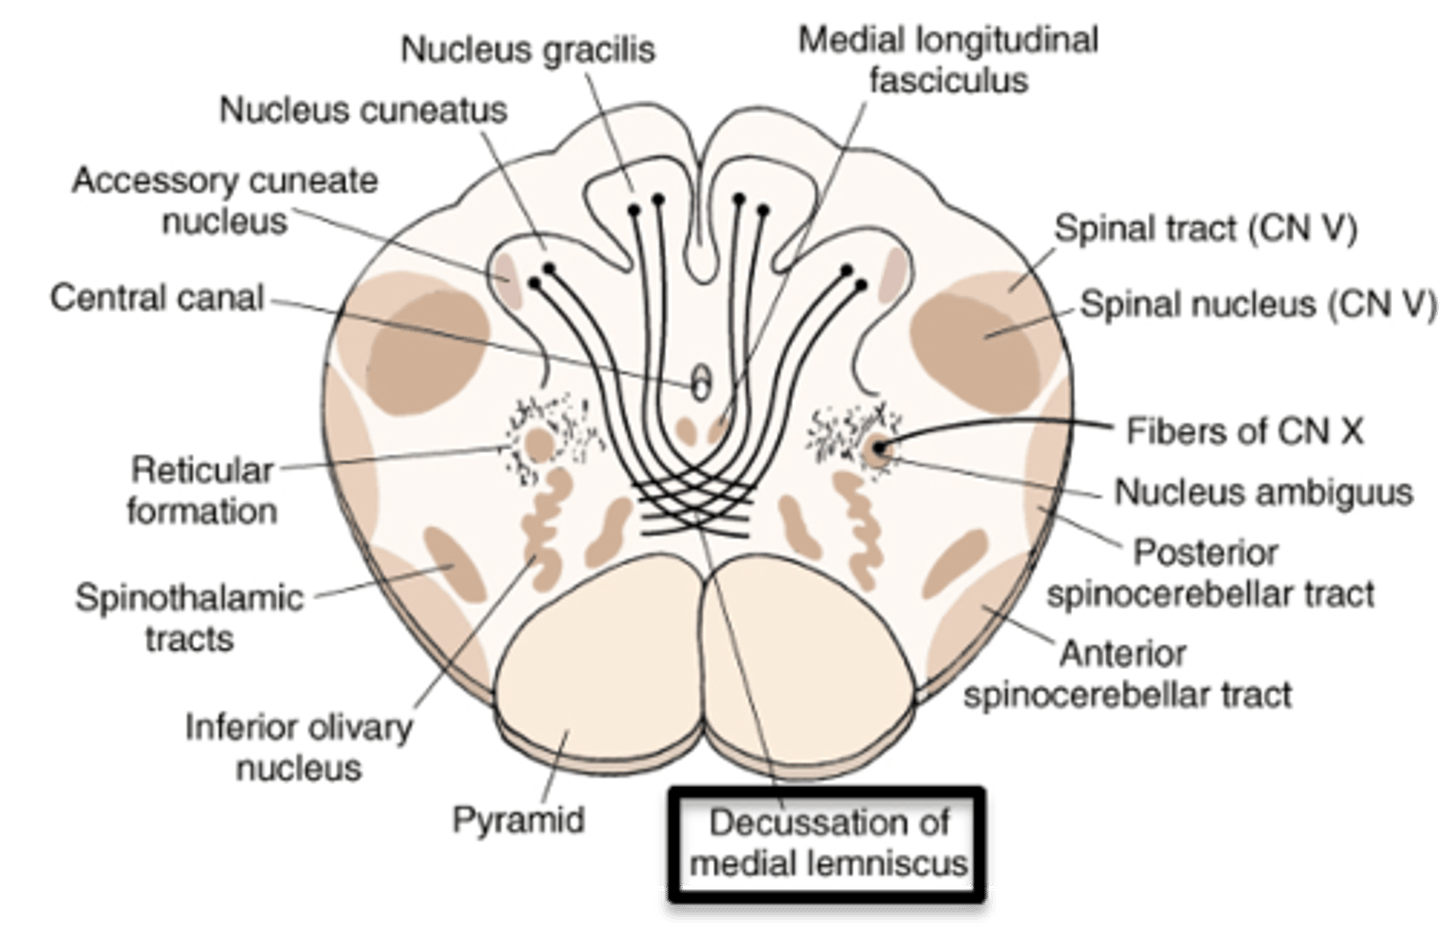

what are the 4 divisions of the spinal cord?

1. cervical

2. thoracic

3. lumbar

4. sacral

which division of the spinal cord is oval in shape, has a large amount of white matter, and includes an enlargement in the lower region?

cervical; cervical enlargement at C4-T1

which division of the spinal cord is round, with small anterior and posterior horns, and lateral horns present?

thoracic

which division of the spinal cord is round, has less white matter than any other levels, has large anterior and posterior horns forming an enlargement throughout the entire division?

lumbar; lumbosacral enlargement from T11-S1

which division of the spinal cord is the most round and smaller than the lumbar division, mainly containing gray matter, but also a thin shell of white matter?

sacral